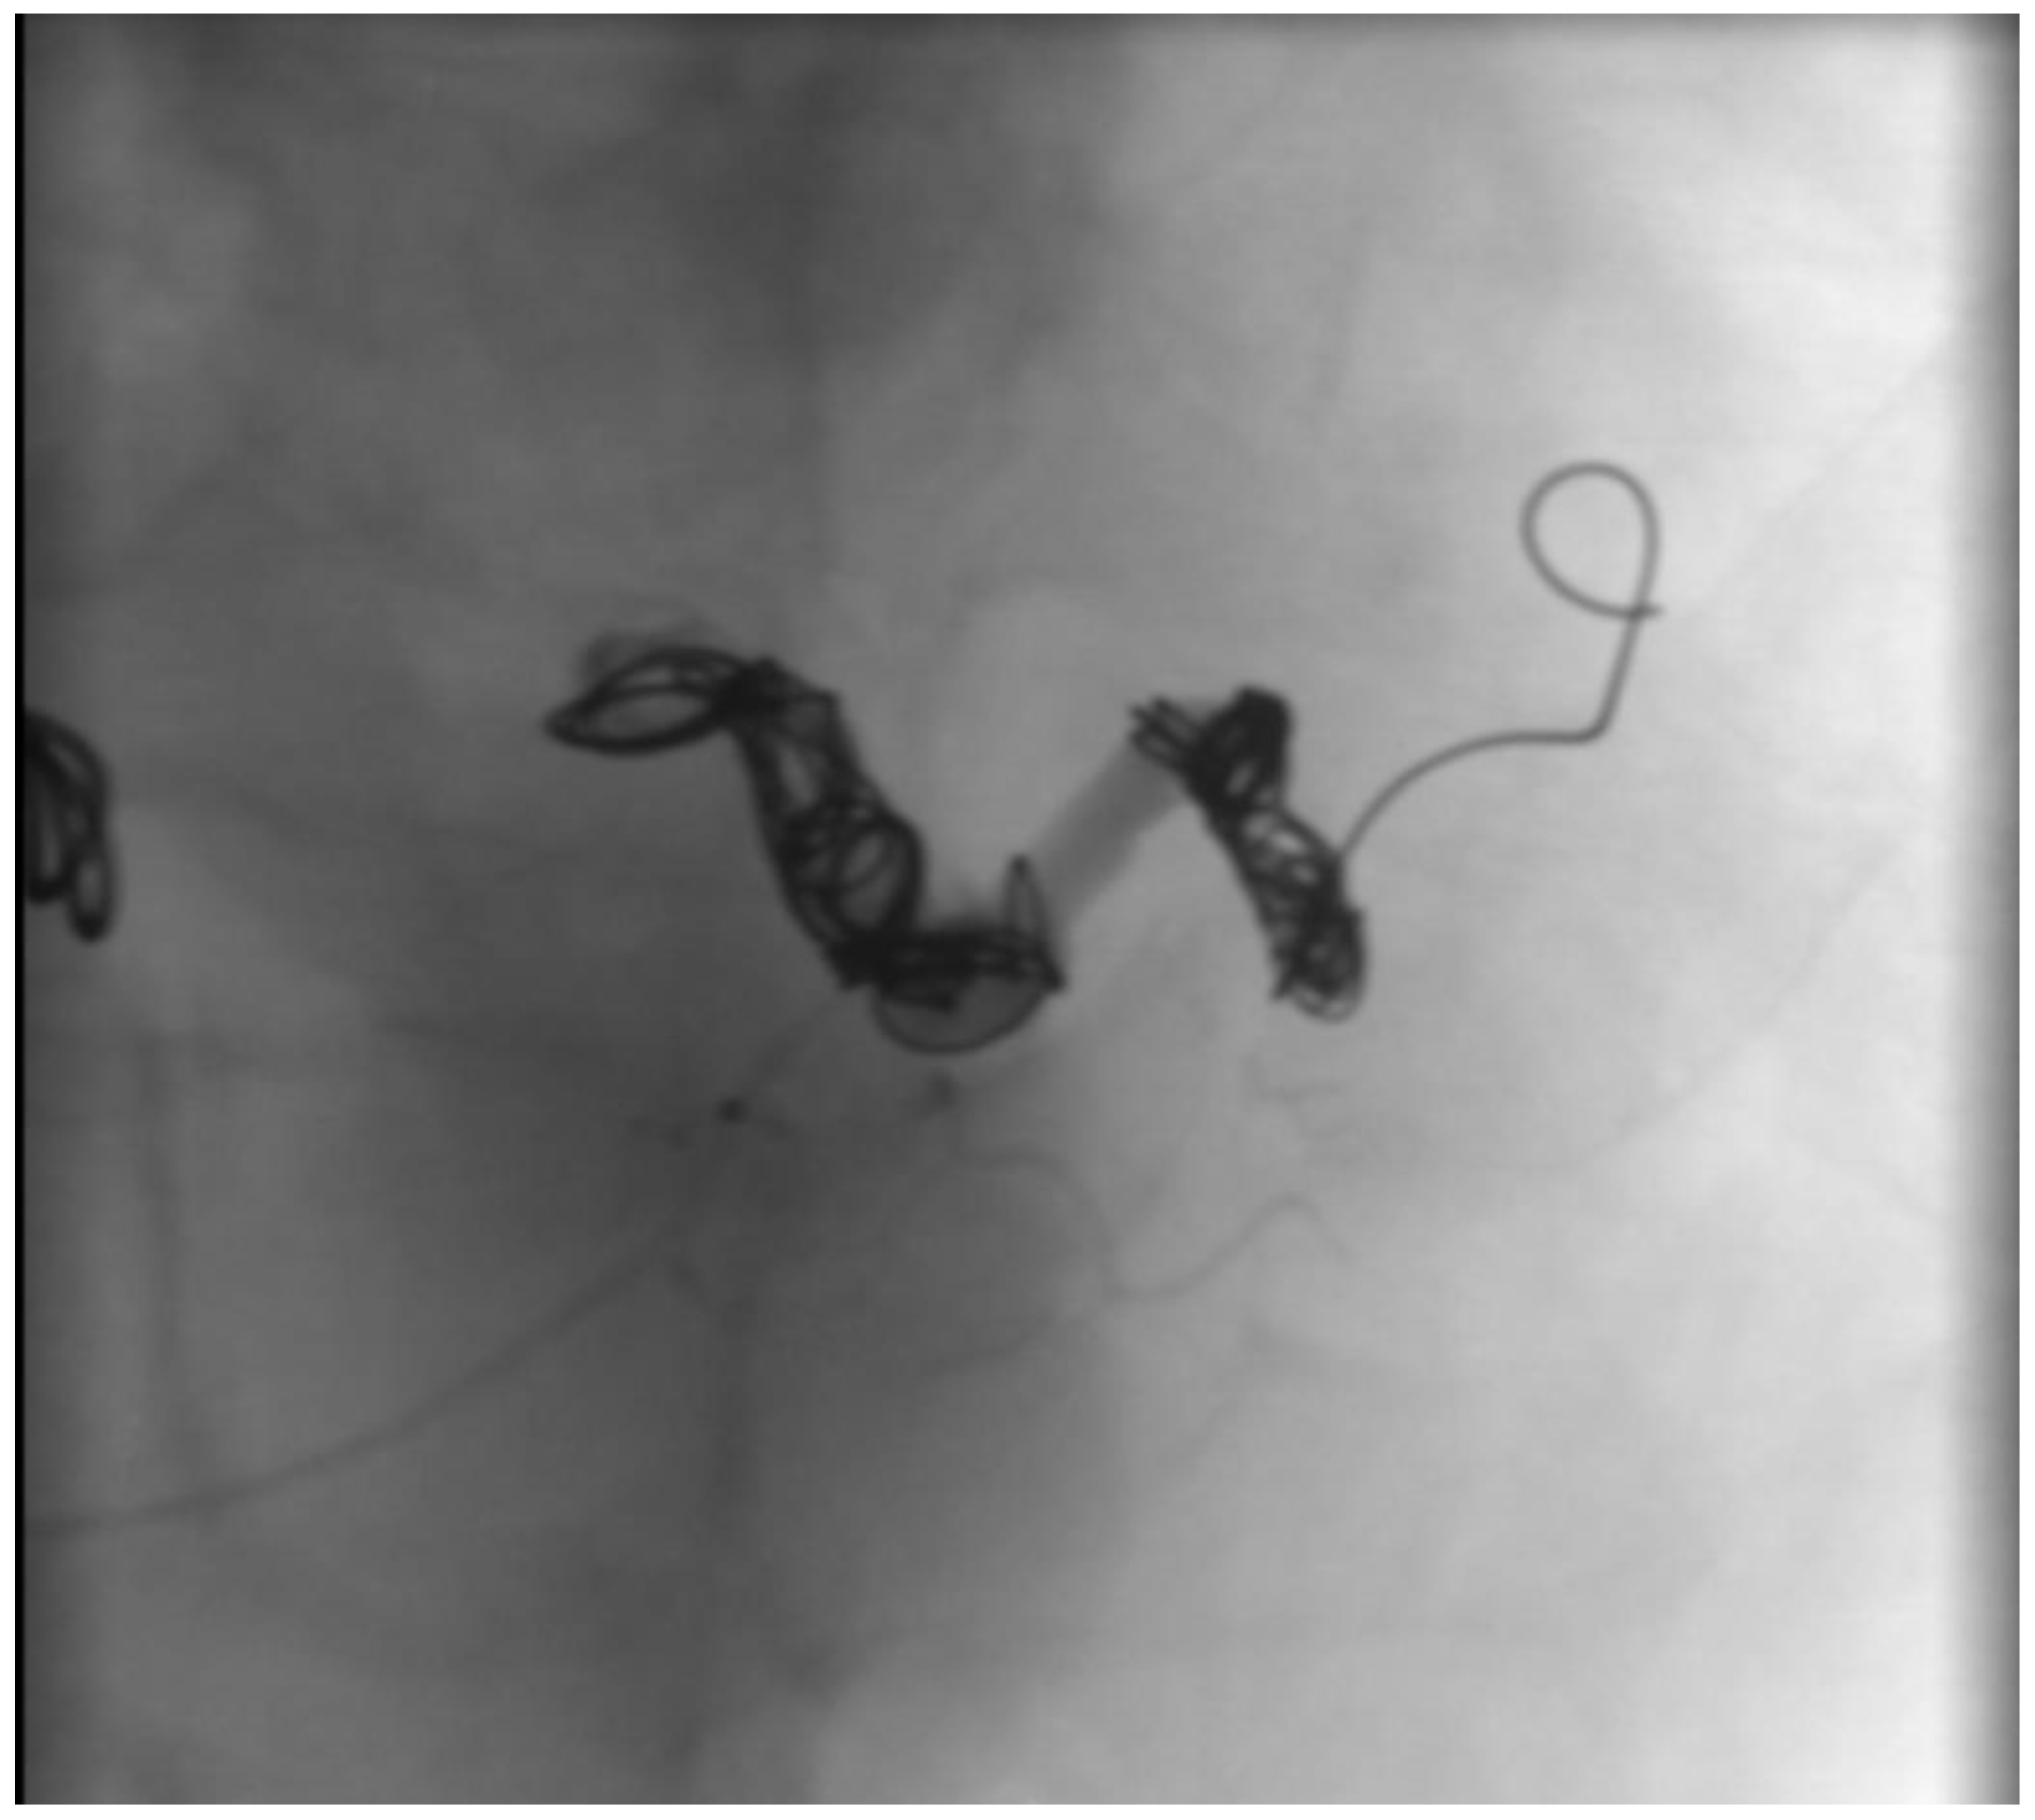

2.1. Case Report